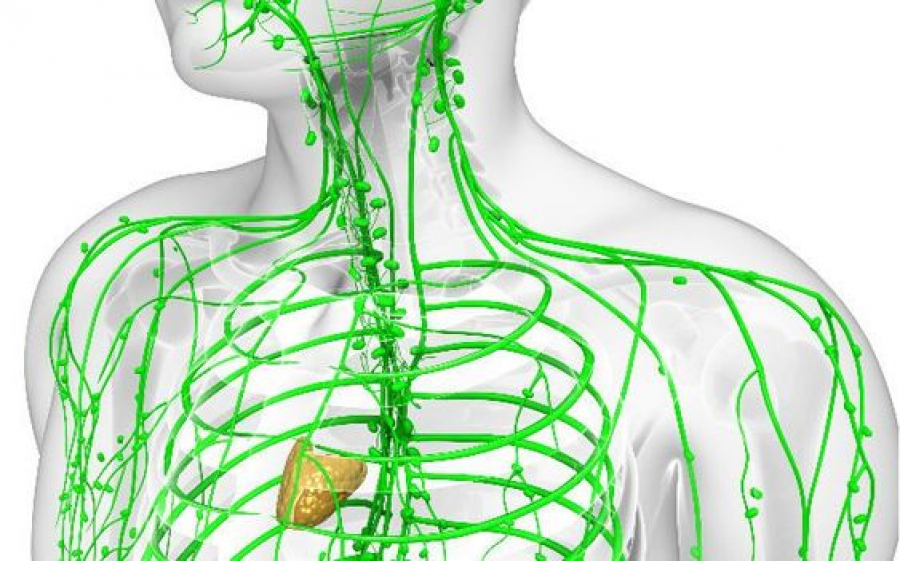

Лимфната система има имунна функция: тя отстранява чуждите частици, бактериите, вирусите и отпадъчните продукти, които попадат в организма.